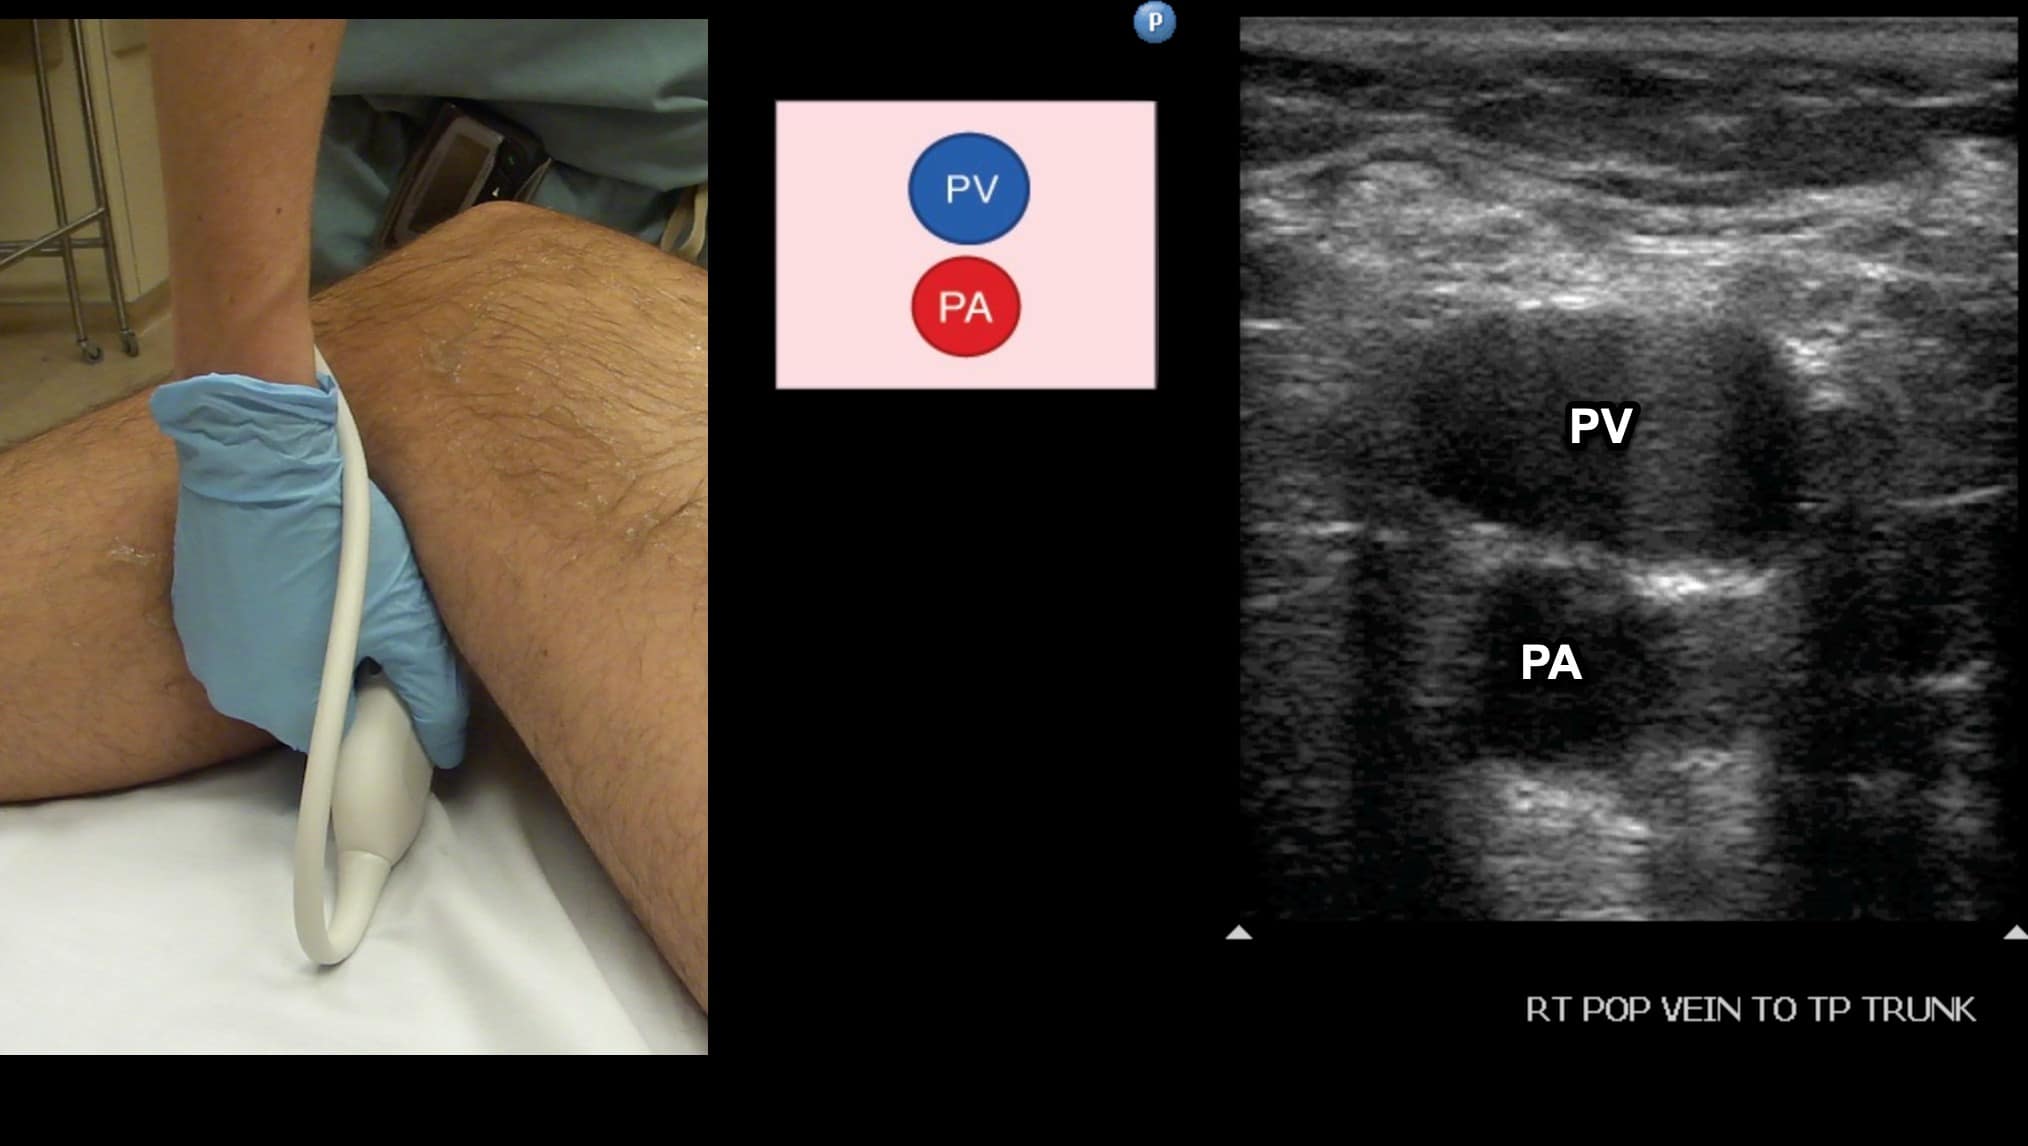

The PV is visualized with the knee flexed to about 30 degrees so the transducer can be placed in the posterior fossa (Figure 10). The popliteal vein is located anatomically posterior to the popliteal artery. Note that since scanning is from the back of the leg, the PV will be noted in the near field (Figure 11). The PV should be followed and compressed at intervals until the popliteal vein trifurcates. The examination is completed at this point. (See video for scanning protocol.)

Figure 10. Transducer placement for evaluation of the popliteal vein (PV). The leg is flexed to approximately 30 degrees. The transducer indicator is directed toward the patient’s right.

Figure 11. Split screen demonstrating transverse window of the popliteal vein (PV). Note that since we are scanning in a posterior to anterior direction that the PV is seen in the near field even though it is anatomically posterior to the popliteal artery (PA).